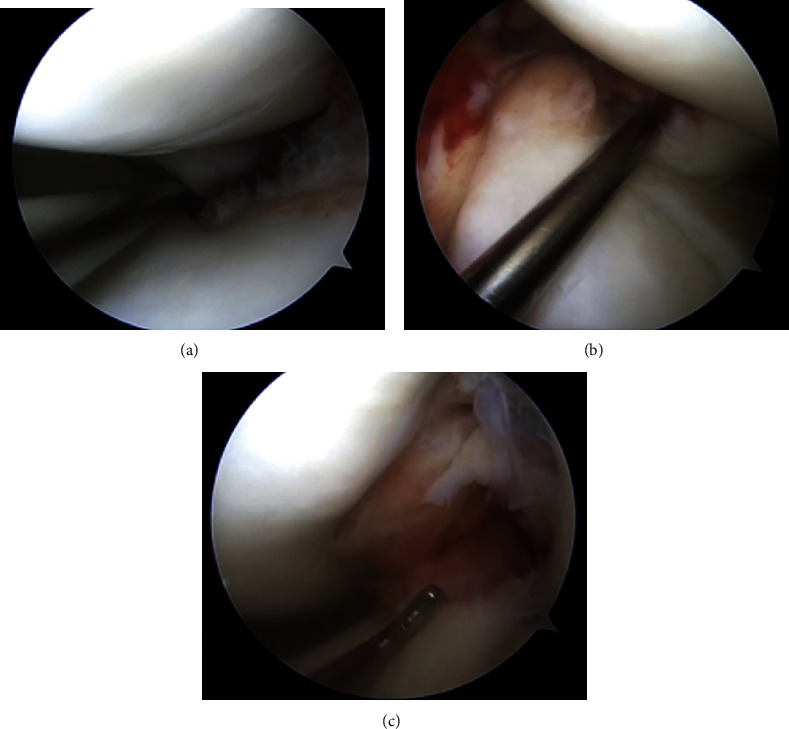

在急性前十字韧带(ACL)断裂的情况下,合并内侧和外侧后半月板根撕裂的情况极为罕见。以下病例报告显示,一名高中橄榄球运动员在训练中做旋转动作时膝盖非接触性受伤。患者是一名 17 岁的高中橄榄球防守后卫,受伤一周后到诊所就诊,主诉膝关节持续疼痛,伴有肿胀,活动范围(ROM)受限,并主诉膝关节不稳定。体格检查时发现患者膝关节前十字韧带松弛。磁共振成像(MRI)显示前交叉韧带中段完全撕裂,内侧半月板后角信号增强,外侧半月板局部无明显病变迹象。患者接受了前交叉韧带重建术(ACLR),术中发现内侧和外侧根部均有撕裂。手术采用标准的髌腱骨(BTB)自体移植前交叉韧带重建术,利用经胫骨牵引法对内侧和外侧根部进行联合修复。其临床意义在于,半月板根部撕裂伴有前交叉韧带撕裂很难在术前核磁共振成像中诊断出来,尤其是在侧方,因此在关节镜检查时仔细评估两个半月板根部至关重要。此外,为避免与前交叉韧带胫骨隧道合并,仔细创建经胫骨修复所需的半月板根修复隧道至关重要。

Combined medial and lateral posterior meniscal root tears in the setting of an acute anterior cruciate ligament (ACL) rupture are extremely rare. The following case report demonstrates a high school football player who sustained a noncontact knee injury while performing a spin move at practice. The patient is a 17-year-old high school football defensive end who was presented to the clinic 1 week following the injury complaining of persistent knee pain with associated swelling, limited range of motion (ROM), and complaint of instability. During physical examination, the patient was found to have anterior cruciate laxity. Magnetic resonance imaging (MRI) demonstrated a complete midsubstance tear of the ACL and increased signal within the posterior horn of the medial meniscus with no obvious signs of pathology localized to the lateral meniscus. ACL reconstruction (ACLR) was performed and intraoperatively, both medial and lateral root tears were found. A standard bone patellar-tendon bone (BTB) autograft ACLR was performed with combined medial and lateral root repair utilizing a transtibial pull-out method for both. The clinical importance is root tears with associated ACL tears can be hard to diagnose on preoperative MRI, especially laterally, so careful assessment of both meniscal roots at the time of arthroscopy is critical. Furthermore, careful creation of the needed root repair tunnels for transtibial repair is critical to avoid coalescence with the ACL tibial tunnel.